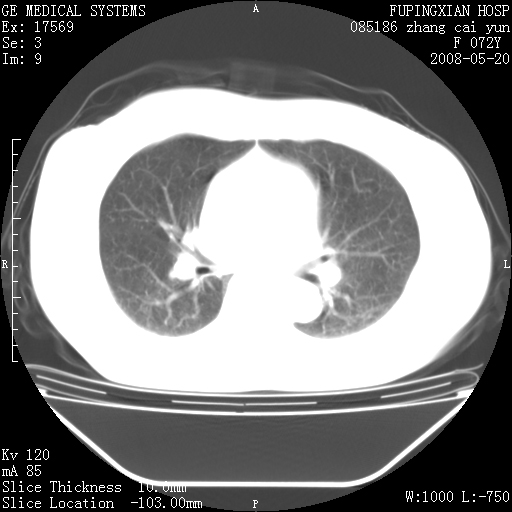

标题: CT13542:发热,咳嗽数日,经抗菌素治疗好转,请大家看排除 [打印本页]

标题: CT13542:发热,咳嗽数日,经抗菌素治疗好转,请大家看排除

上叶支气管略变窄并通畅,内壁光滑。考虑:单纯阻塞性肺炎!

右上叶支气管走行自然,未见明显管壁增厚等征像,另左主支气管起始部可见异常腔道向左侧延展左肺动脉干后方,与左下叶支气管相通,为左下叶支气管变异?

有节段性阻塞性肺炎与不张,近段支气管狭窄,周围散在肿大淋巴结影,以周围型肺癌可能性大,建议纤支镜检查。

右肺上叶实变影,内见支气管充气征,右上叶支气管通畅,肺门区未见软组织密度影,抗炎治疗有效,考虑炎症,建议继续抗炎治疗复查。

右上肺实变,间内有支气管充气征,考虑炎症,建议抗炎后复查